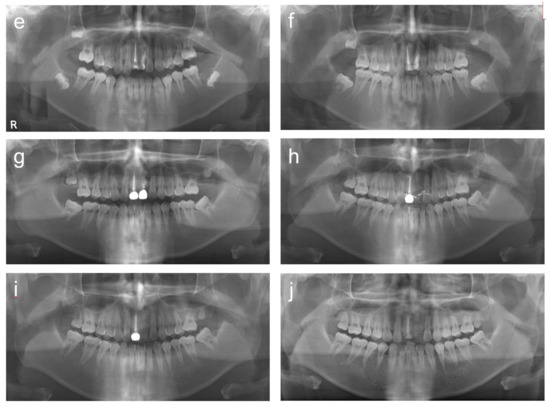

2. Cases

2.2. Case 2

2.3. Case 3

2.4. Case 4

2.5. Case 5